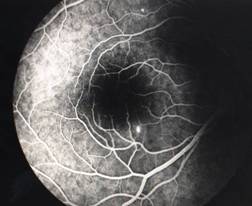

CENTRAL RETINAL VEIN OCCLUSION (CRVO) |

The actual mechanisms producing the clinical picture of central retinal vein occlusion may be roughly divided into those conditions that produce a physical blockage at the level of the lamina cribrosa, and those conditions in which hemodynamic factors result in an obstruction to the flow of blood. These mechanisms probably coexist in many patients with Central Vein Occlusion.

Confluent hemorrhages are the most prominent ophthalmoscopic feature of an acute ischemic central retinal vein occlusion These hemorrhages occur in a wide variety of shapes and sizes; they are usually concentrated in the posterior pole, but may be seen throughout the retina. Many hemorrhages are flame shaped, reflecting the orientation of the nerve fibers. Dot and punctate hemorrhages are interspersed and indicate involvement of the deeper retinal layers. Bleeding may be extensive, erupting through the internal limiting membrane to form a preretinal hemorrhage or extending into the vitreous. Small dot hemorrhages may be seen either isolated or clustered around small venules. The entire venous tree is tortuous, engorged, dilated, and dark. The retina is edematous, particularly in the posterior pole; some of this edema may obscure portions of the retinal vessels. Cotton-wool patches (soft exudates) are often present. The disc margin is blurred or obscured, and the precapillary arterioles appear engorged. Splinter hemorrhages and edema are present on the disc surface and extend into the surrounding retina. The physiologic cup is filled, and the venous pulse is absent. The arterioles, often overlooked because of the other more striking pathologic features, are frequently narrowed. Sometimes in central retinal vein occlusion of acute onset, the fundus picture is less dramatic, and all of the findings previously discussed may be present, but to a lesser degree. Vision depends on extent of macular involvement